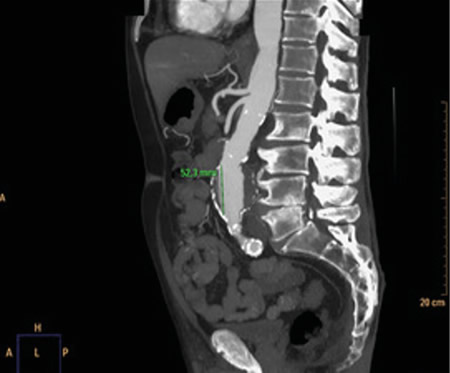

Figura 1